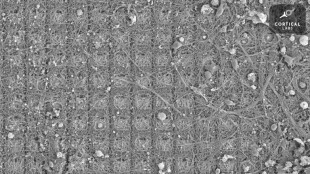

Des scientifiques ont créé pour la première fois des œufs en utilisant les cellules de souris mâles, et obtenu sept souriceaux issus de deux pères, selon une étude publiée mercredi et qualifiée de "révolutionnaire" par un chercheur.